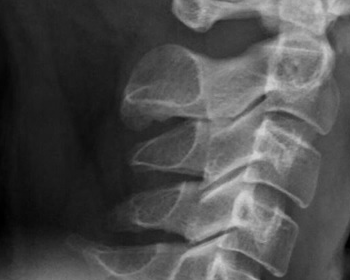

What is Cervical Calcification?

Calcification occurs when calcium accumulates in cells, arteries, or organs. This accumulation often hardens and disturbs the body’s natural functions. Calcium circulates through the bloodstream. This substance is also present in every living cell. Calcification can therefore present in practically every area of the body. Calcification is a form of intervertebral disc degeneration that most commonly affects the cervical portion of the spine.

Disc calcification is typically accompanied by significant indications and symptoms in children, particularly in the cervical spine. In instances of cervical disc calcification, the natural history reported symptoms, and physical and x-ray findings are all very similar. This suggests that this condition must be treated as its clinical entity.

Cervical calcification is generally asymptomatic. Calcium deposits are more commonly found on X-rays, such as mammograms, and thus are more readily detected by medical professionals.